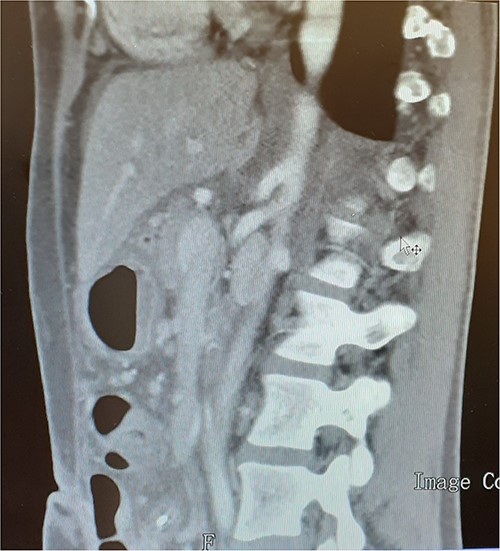

A 37-year-old woman with autoimmune thyroiditis, epilepsy, anti-erythrocyte S antibody and with suspected mixed cryoglobulinemia under study was evaluated for recurrent postprandial abdominal pain with 6 months of evolution, fullness and vomiting with copious meals and weight loss of about 7 kg in 6 months, having already performed a computed tomography angiography (CTA) that revealed MALS (Fig.1). In collaboration with the General Surgery Department, a section of the MAL and lysis of the adhesions by laparoscopic approach was performed. On the third postoperative day, the patient developed a chylous fistula that resolved with conservative strategy including oral diet discontinuation, parenteral nutrition and octreotide. At 1 year follow-up, the patient showed clinical improvement in abdominal pain and food tolerance, and imagiological improvement (Fig.2).

Compression of the celiac artery origin compatible with MALS; note the indentation on the superior wall of the celiac artery, leading to focal stenosis and absence of arterial wall thickening close to the stenosis.